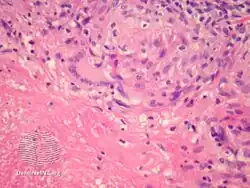

Histopathology

Lupus miliaris disseminatus faciei/pathology -